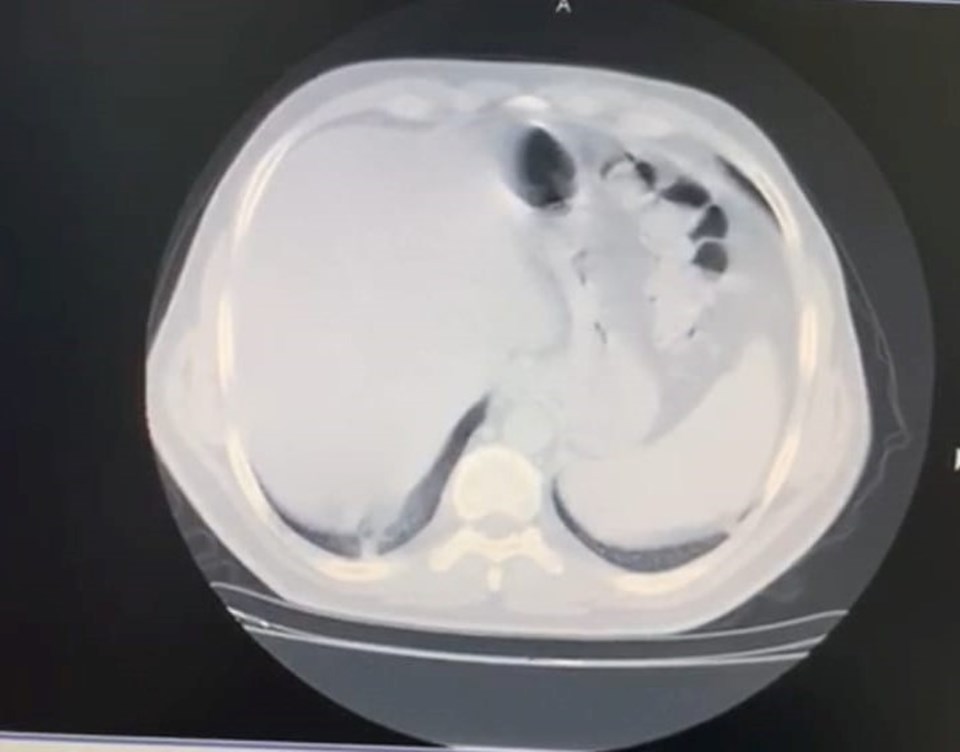

AKCİĞERİN YÜZDE 70’İNDE TUTULMA GÖRÜLDÜ

Evdeki 8 günlük sürecin ardından durumu ağırlaşan Civil, ikinci kez çekilen tomografide akciğerinde yaygın bir corona virüs zatürre tutulumu görüldüğüne dikkat çekerek şunları söyledi; “Çok korkunç bir görüntü vardı. O görüntüyü görünce psikolojik olarak da çok etkilendim. Daha sonra hastaneye yatırıldım ve ateşim 41 derece civarındaydı. Oksijen satürasyonum da 70’lere kadar düştü. Yoğun bakım hastalarında kullanılan bir ilaca başlandı. Hastaneye yattığımın ilk 3 günü çok kritikti. Genel durumum bu 3 gün içerisinde yavaş yavaş bozulmaya başlamıştı. Nefes alamıyordum ve boğuluyordum. Sıkıntılı ve sancılı bir süreçti"

Tomografisinde görülen bulguların ne anlama geldiğini bildiği için ümitsizliğe kapıldığını ifade eden İstanbul Gelişim Üniversitesi Sağlık Bilimleri Yüksekokulu’ndan Dr. Öğretim Üyesi Celal Civil, “Vital bulgularım çok kötüydü. Acaba bu virüsü atlatamayacak mıyım? Yolun sonuna mı geldik? Buraya kadar mı? diye çok düşündüm. Klinik olarak kötü durumdaydım, radyolojik ve laboratuvar sonuçlarım da çok kötüydü. Nefes darlığı çok kötü bir duygu. Boğulma hissi yaşıyorsunuz. Boşuna nefes alıyormuş gibi hissediyorsunuz çünkü ciğerler corona virüs tarafından tutulmuş durumda. Kafanızı suya sokup nefes almaya çalışmaya benziyor. Dakikada 8 litre oksijenle hayata tutunmaya çalışıyordum. 1 hafta boyunca oksijene bağımlı bir şekilde hastanede yattım. İlk günler dip yaşadım, hatta 2 kez yoğun bakım ekibi benim için geldi, entübasyon dahi düşünüldü” dedi.